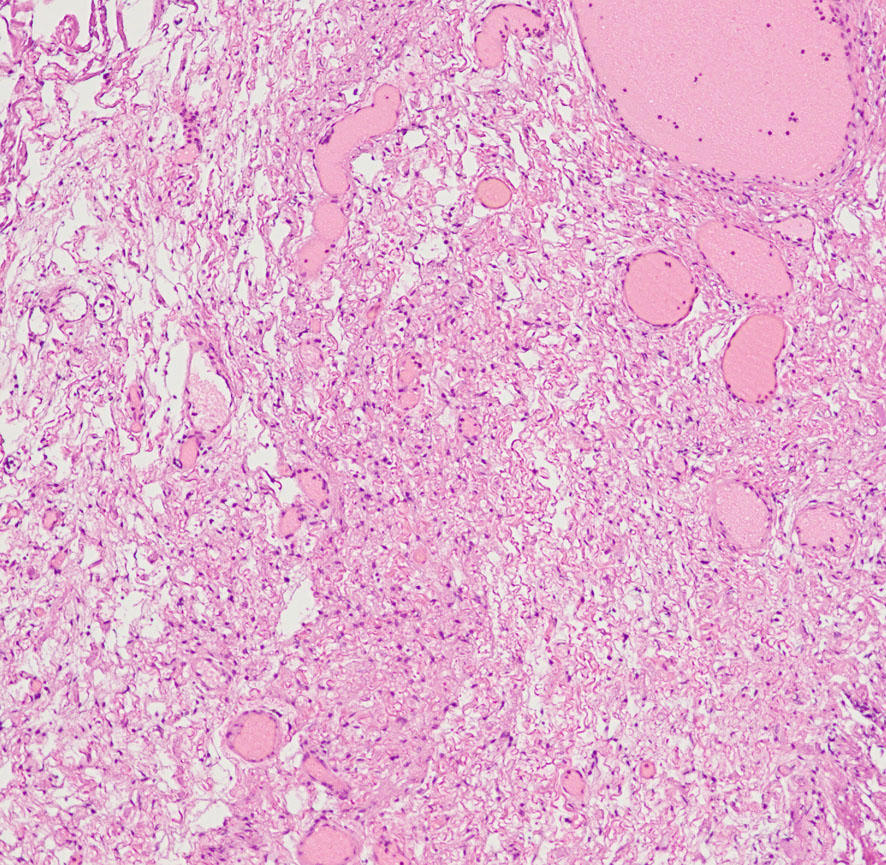

Antoni type A(密な部分)とAntoni type B(そな部分)の混在

紡錐型の核を有する腫瘍細胞で構成されます。左側の写真のように,古典的病理所見として,束状 fascicular に配列する密な組織である Antoni A Typeと網状 reticular で疎な組織である Antoni B Typeが混在するパターンを示します。神経鞘腫では多少の核の異型性がみられても悪性像とはいえません。嚢胞を形成したり,時には毛細血管拡張 simple hemangioma を思わせるような著明な血管の増生があり腫瘍内出血をきたすことがあります。

30代男性の迷走神経鞘腫です。右のように活発に増殖してstreaming patternをとる部分と,左のようにのう胞形成しながら退縮変性 degenerative change している部分が混在しています。若年者の神経鞘腫でも退縮変性はみられます。